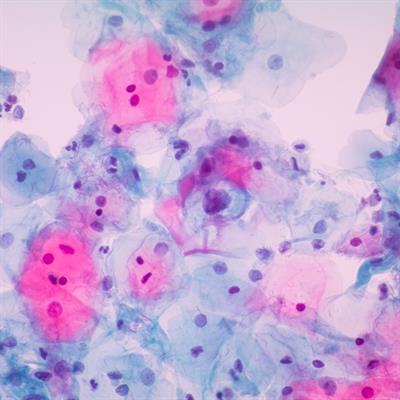

Research Topic Research topic image